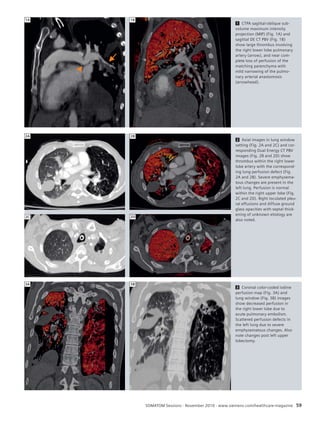

56 Dual Source, Dual Energy CT:

Improvement of Lung Perfusion

Within 5 Hours in a Patient With

Acute Pulmonary Embolism